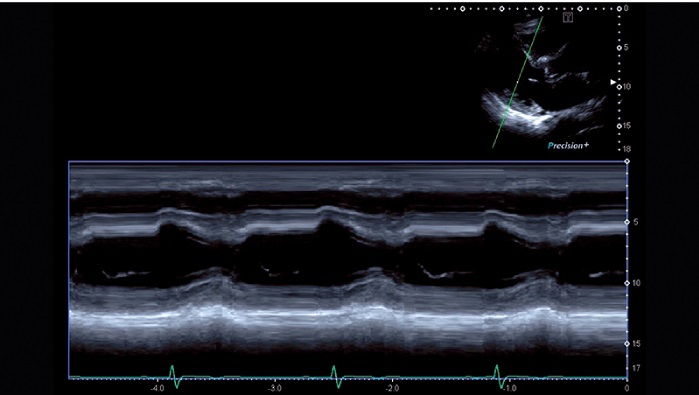

УЗИ аппарат Canon Aplio i900 — универсальный сканер премиального класса. Оснащенная обновленным пакетом 4D-функций, система считается лучшей в своем классе для исследования сердца и его визуализации. Технология максимально тщательной обработки изображения позволяет врачам ставить точные диагнозы, основываясь на контрастных и высокодетализированных снимках.

- Четырехмерная визуализация сердца в повседневной клинической практике - лучшая в своем классе

- Quad-Chamber Tracking - отображает кинетику нескольких камер сердца на одном экране в режиме 3D, вместе с параметрическими кривыми

- 3D/4D сердца: ✔

- Автоматические измерения в кардиологии - фракция выброса, объемы и пр. : ✔

Технология Flex-M позволяет получать анатомически правильные срезы в М-режиме в режиме онлайн, а также на основе сохраненных 2D-изображений с тем же качеством, что и в обычном М-режиме. При анатомическом М-режиме можно вращать курсор под произвольным угл